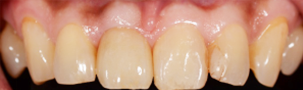

前歯が割れてしまってインプラントをご希望で来院された患者様です。

前歯に亀裂が入ってしまっており、抜歯後、インプラント治療を行いました。

非常に審美的な治療が出来ました。

当院では難しい前歯のインプラントも違和感なくきれいに処置することが出来ます。